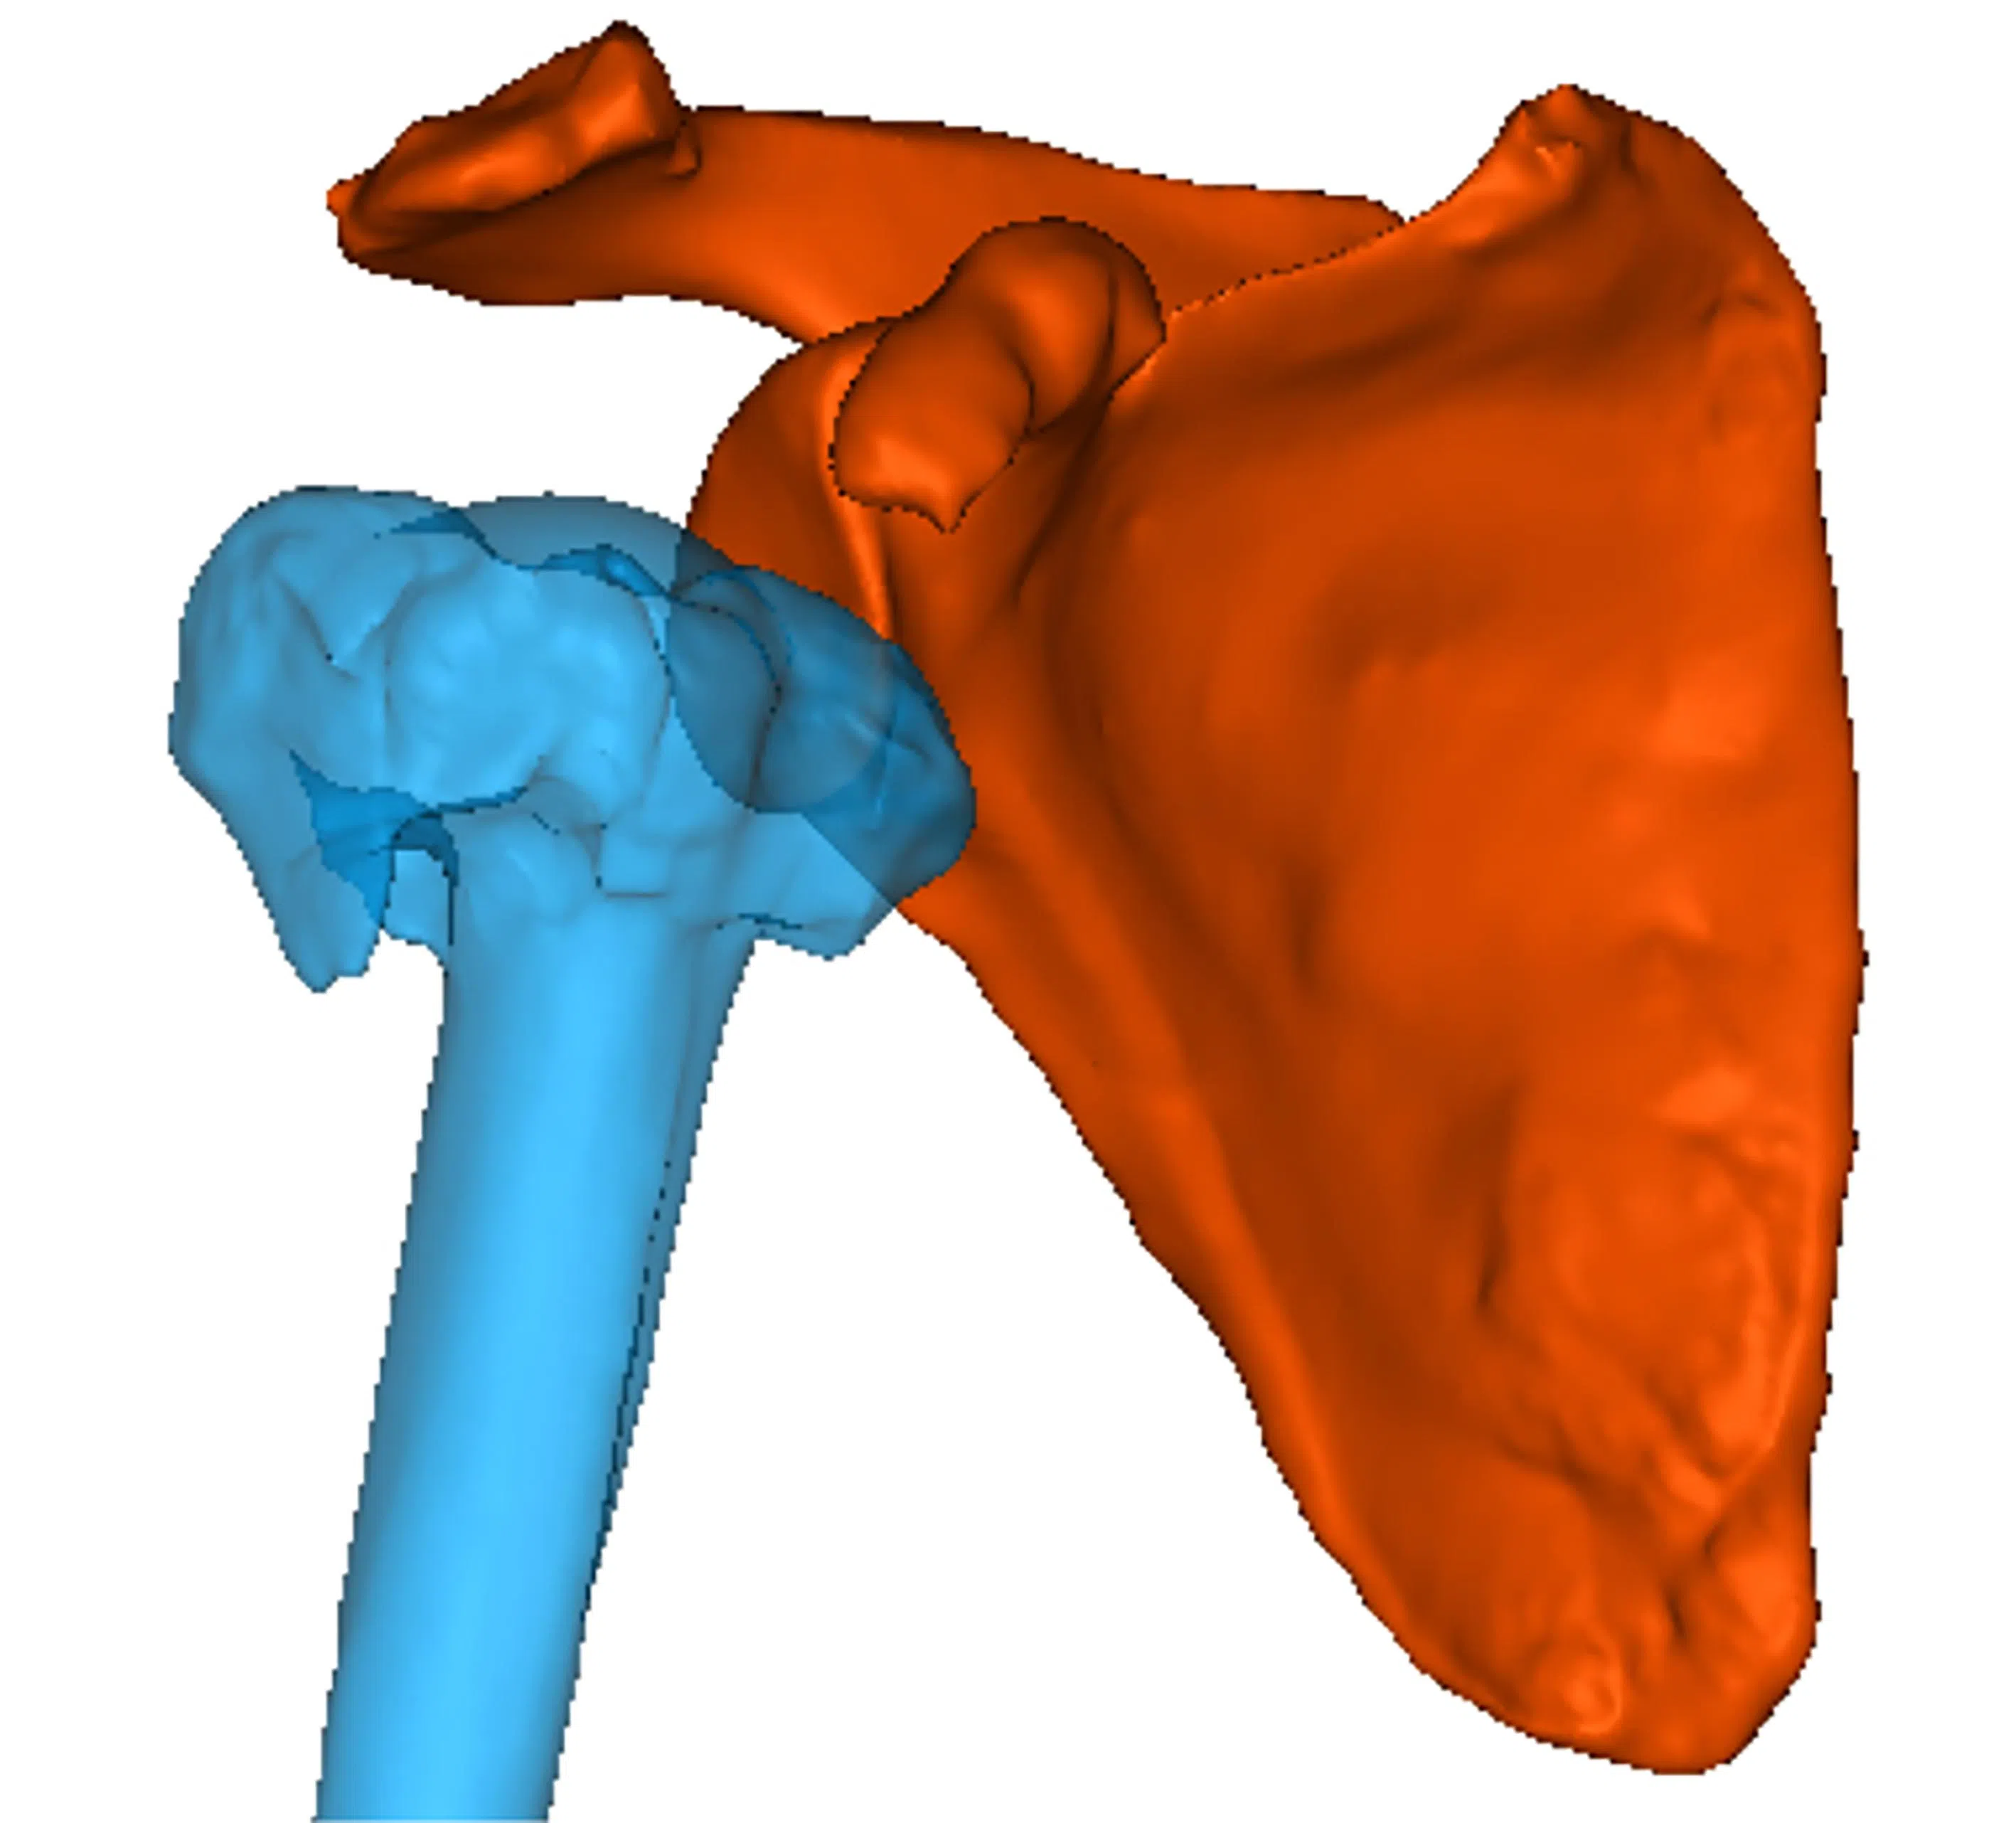

1. A 3D-printed model is created from high-quality images taken via CT scans, magnetic resonance imaging, X-rays, and a patient’s data.

2. A surgeon and a biomechanical engineer create precise digital models. This is to optimise implant positioning and sizing by using virtual surgical planning – a technology-driven, 3D-simulation process to plan and rehearse the procedure.